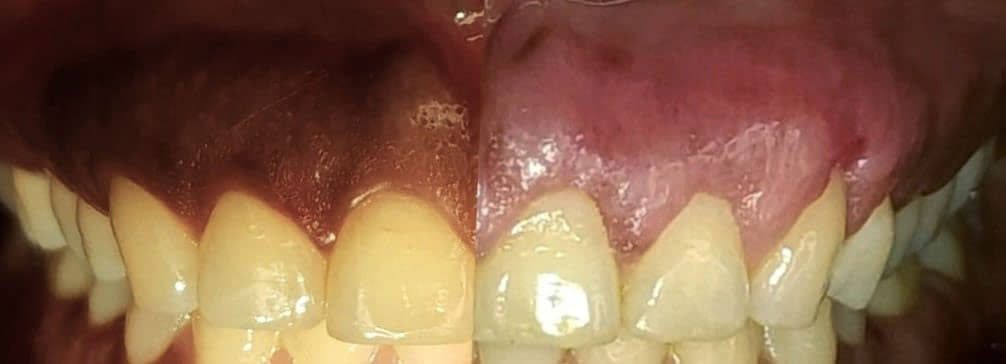

Tratamientos efectivos para combatir la periodontitis

En BIOART, ofrecemos una variedad de tratamientos para combatir la periodontitis. Nuestro equipo de expertos diseñará un plan de tratamiento personalizado para tus necesidades.